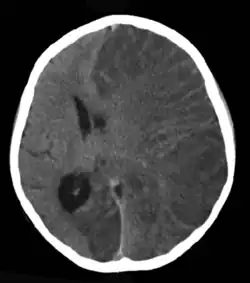

Em 60% a causa é desconhecida, mas algumas doenças neurológicas como a Síndrome de Rasmussen podem causar epilepsia (foto).

A epilepsia pode resultar de uma ampla variedade de fatores genéticos e adquiridos, sendo comum que ambos desempenhem um papel.[53][54] Apesar dos avanços nos métodos diagnósticos, não se identifica uma causa clara em cerca de 60% dos casos. Cada etiologia tem implicações distintas para o diagnóstico, tratamento e prognóstico, tornando essencial a identificação precisa da causa subjacente.[55]